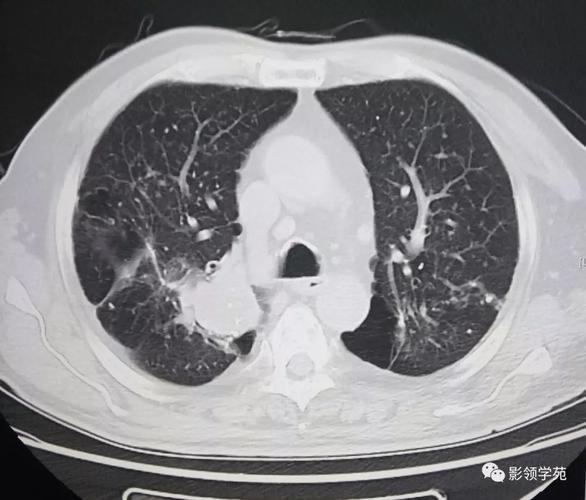

胸闷,咳少量白痰——肺癌,颅内转移瘤